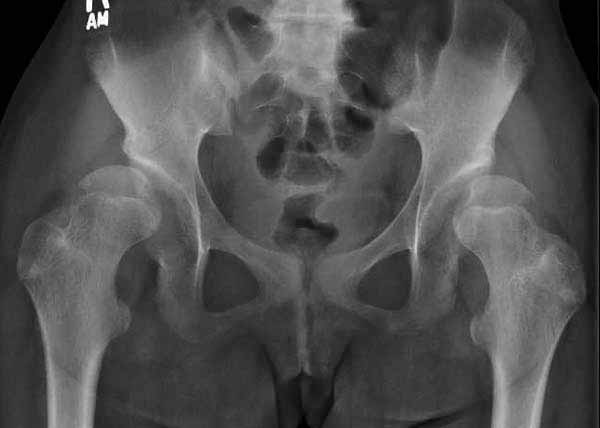

Жалобы на двухсторонние постоянные боли при нагрузке и неустойчивость. Внутренная ротация конечности в суставе более 40 градусов и на рентгенограмме двухсторонний подвывих головки с нарушением линии Шентона, а на боковом снимке с минусовым покрытием головки. МРТ - удлиненная связка и импинджмент (бугор) в шейке.

Первым этапом сделана подготовка к ротационной межвертельной остеотомии, затем капсулотомия с удалением импинджмента и периацетабулярная остеотомия с 40 градусной экстензией и операция закончена 35 градусной наружной ротацией бедра. Запланированный варус не сделан из-за относительно нормального покрытия головки.